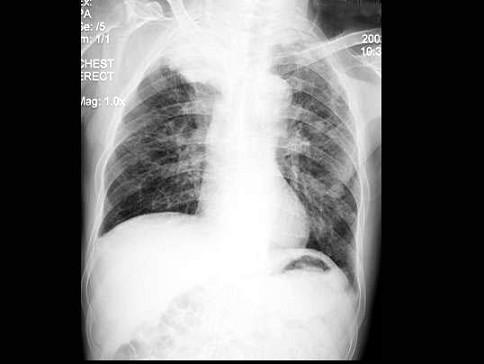

肺癌晚期 胸片

肺癌晚期 胸片,肺癌胸片晚期

但是胸片体检有很大的问题,漏诊率很高,尤其是磨玻璃表现的早期肺癌

肺癌胸片晚期

肺癌胸片

正常肺部胸片

正常胸片和异常胸片